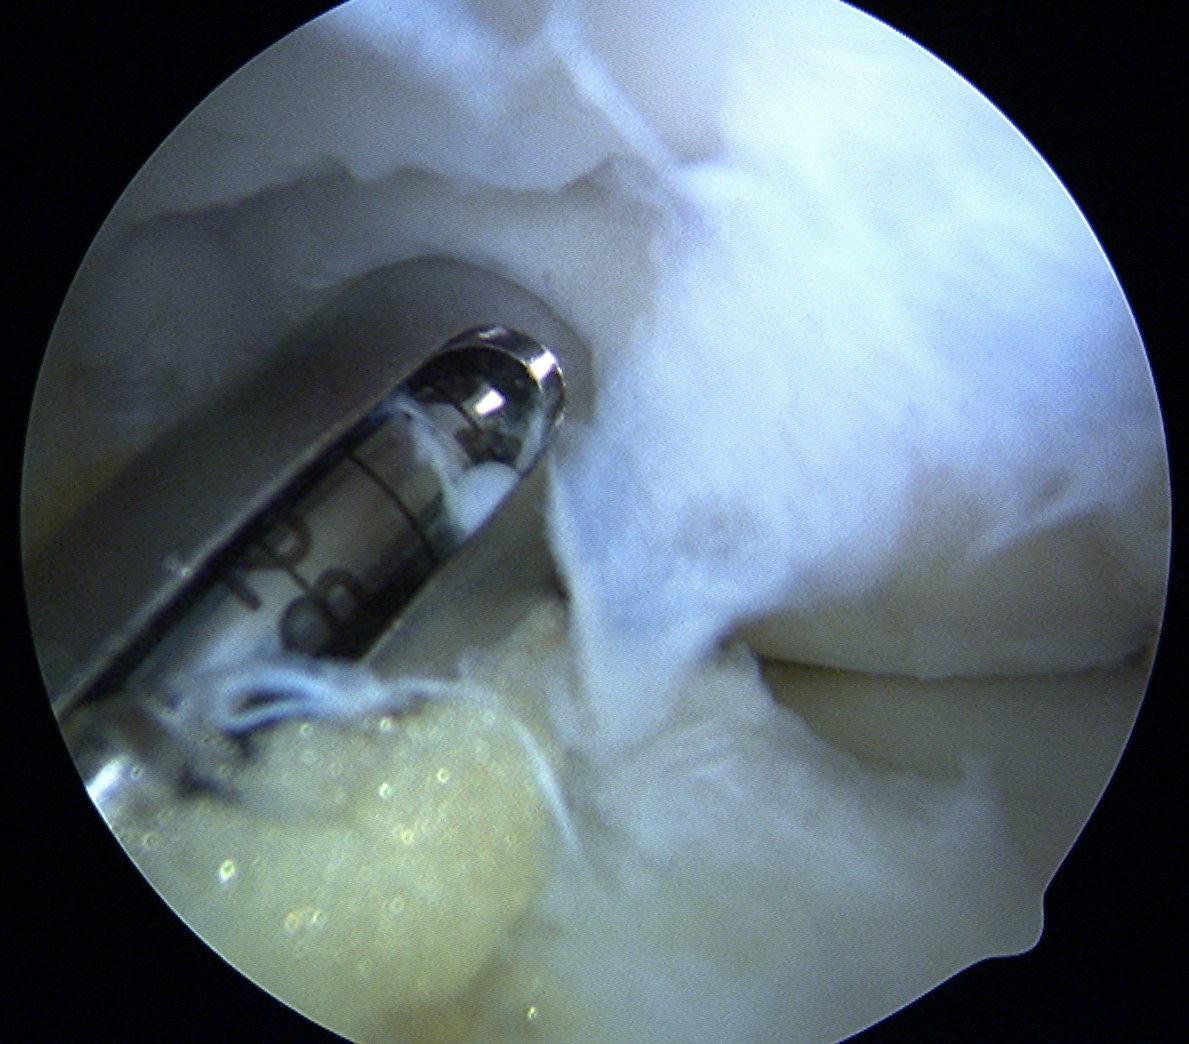

Harvest

- insert 4.5 mm chisel

- hammer to appropriate depth / 20 mm

- twist handle to remove